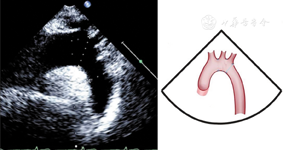

胸骨上窝主动脉弓长轴切面(图24图25)

胸骨上窝主动脉弓长轴切面,显示收缩末期主动脉弓和降主动脉内径测量方法,主动脉弓内径测量位置为无名动脉与左颈总动脉开口位置之间,降主动脉内径测量位置为左锁骨下动脉远心端1 cm处

图24